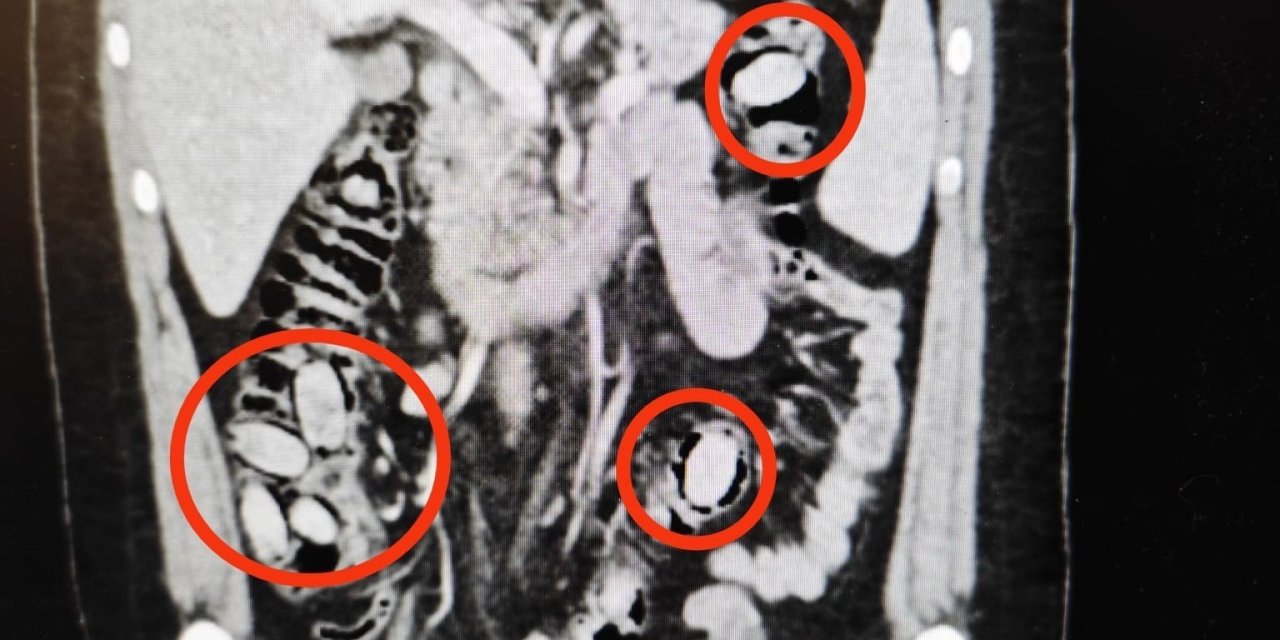

Eskişehir'e 44 kapsül uyuşturucu maddeyi midesinde sokmaya çalışan yabancı uyruklu şahıs polisin dikkati sayesinde yakayı ele verdi.